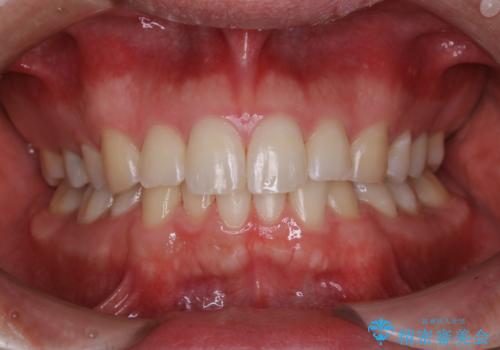

コーヒーの着色落としをPMTCでキレイに

- コーヒが好きで、ステインが付くことが気になるとのことで来院されました。PMTC30分コースを行いました。

PMTCでは、歯のトリートメントも行います。

毎日の歯磨きや飲食などにより、歯の表面に細かい傷がついてしまうため、その傷にステインや汚れなどが付着してしまいます。

トリートメントでは、歯の表面にミネラルや栄養分を補給します。

定期的に専門的な機械や材料を使用してのクリーニングを行うことで、歯質の強化になり、ステインや汚れが付きにくい状態となります。